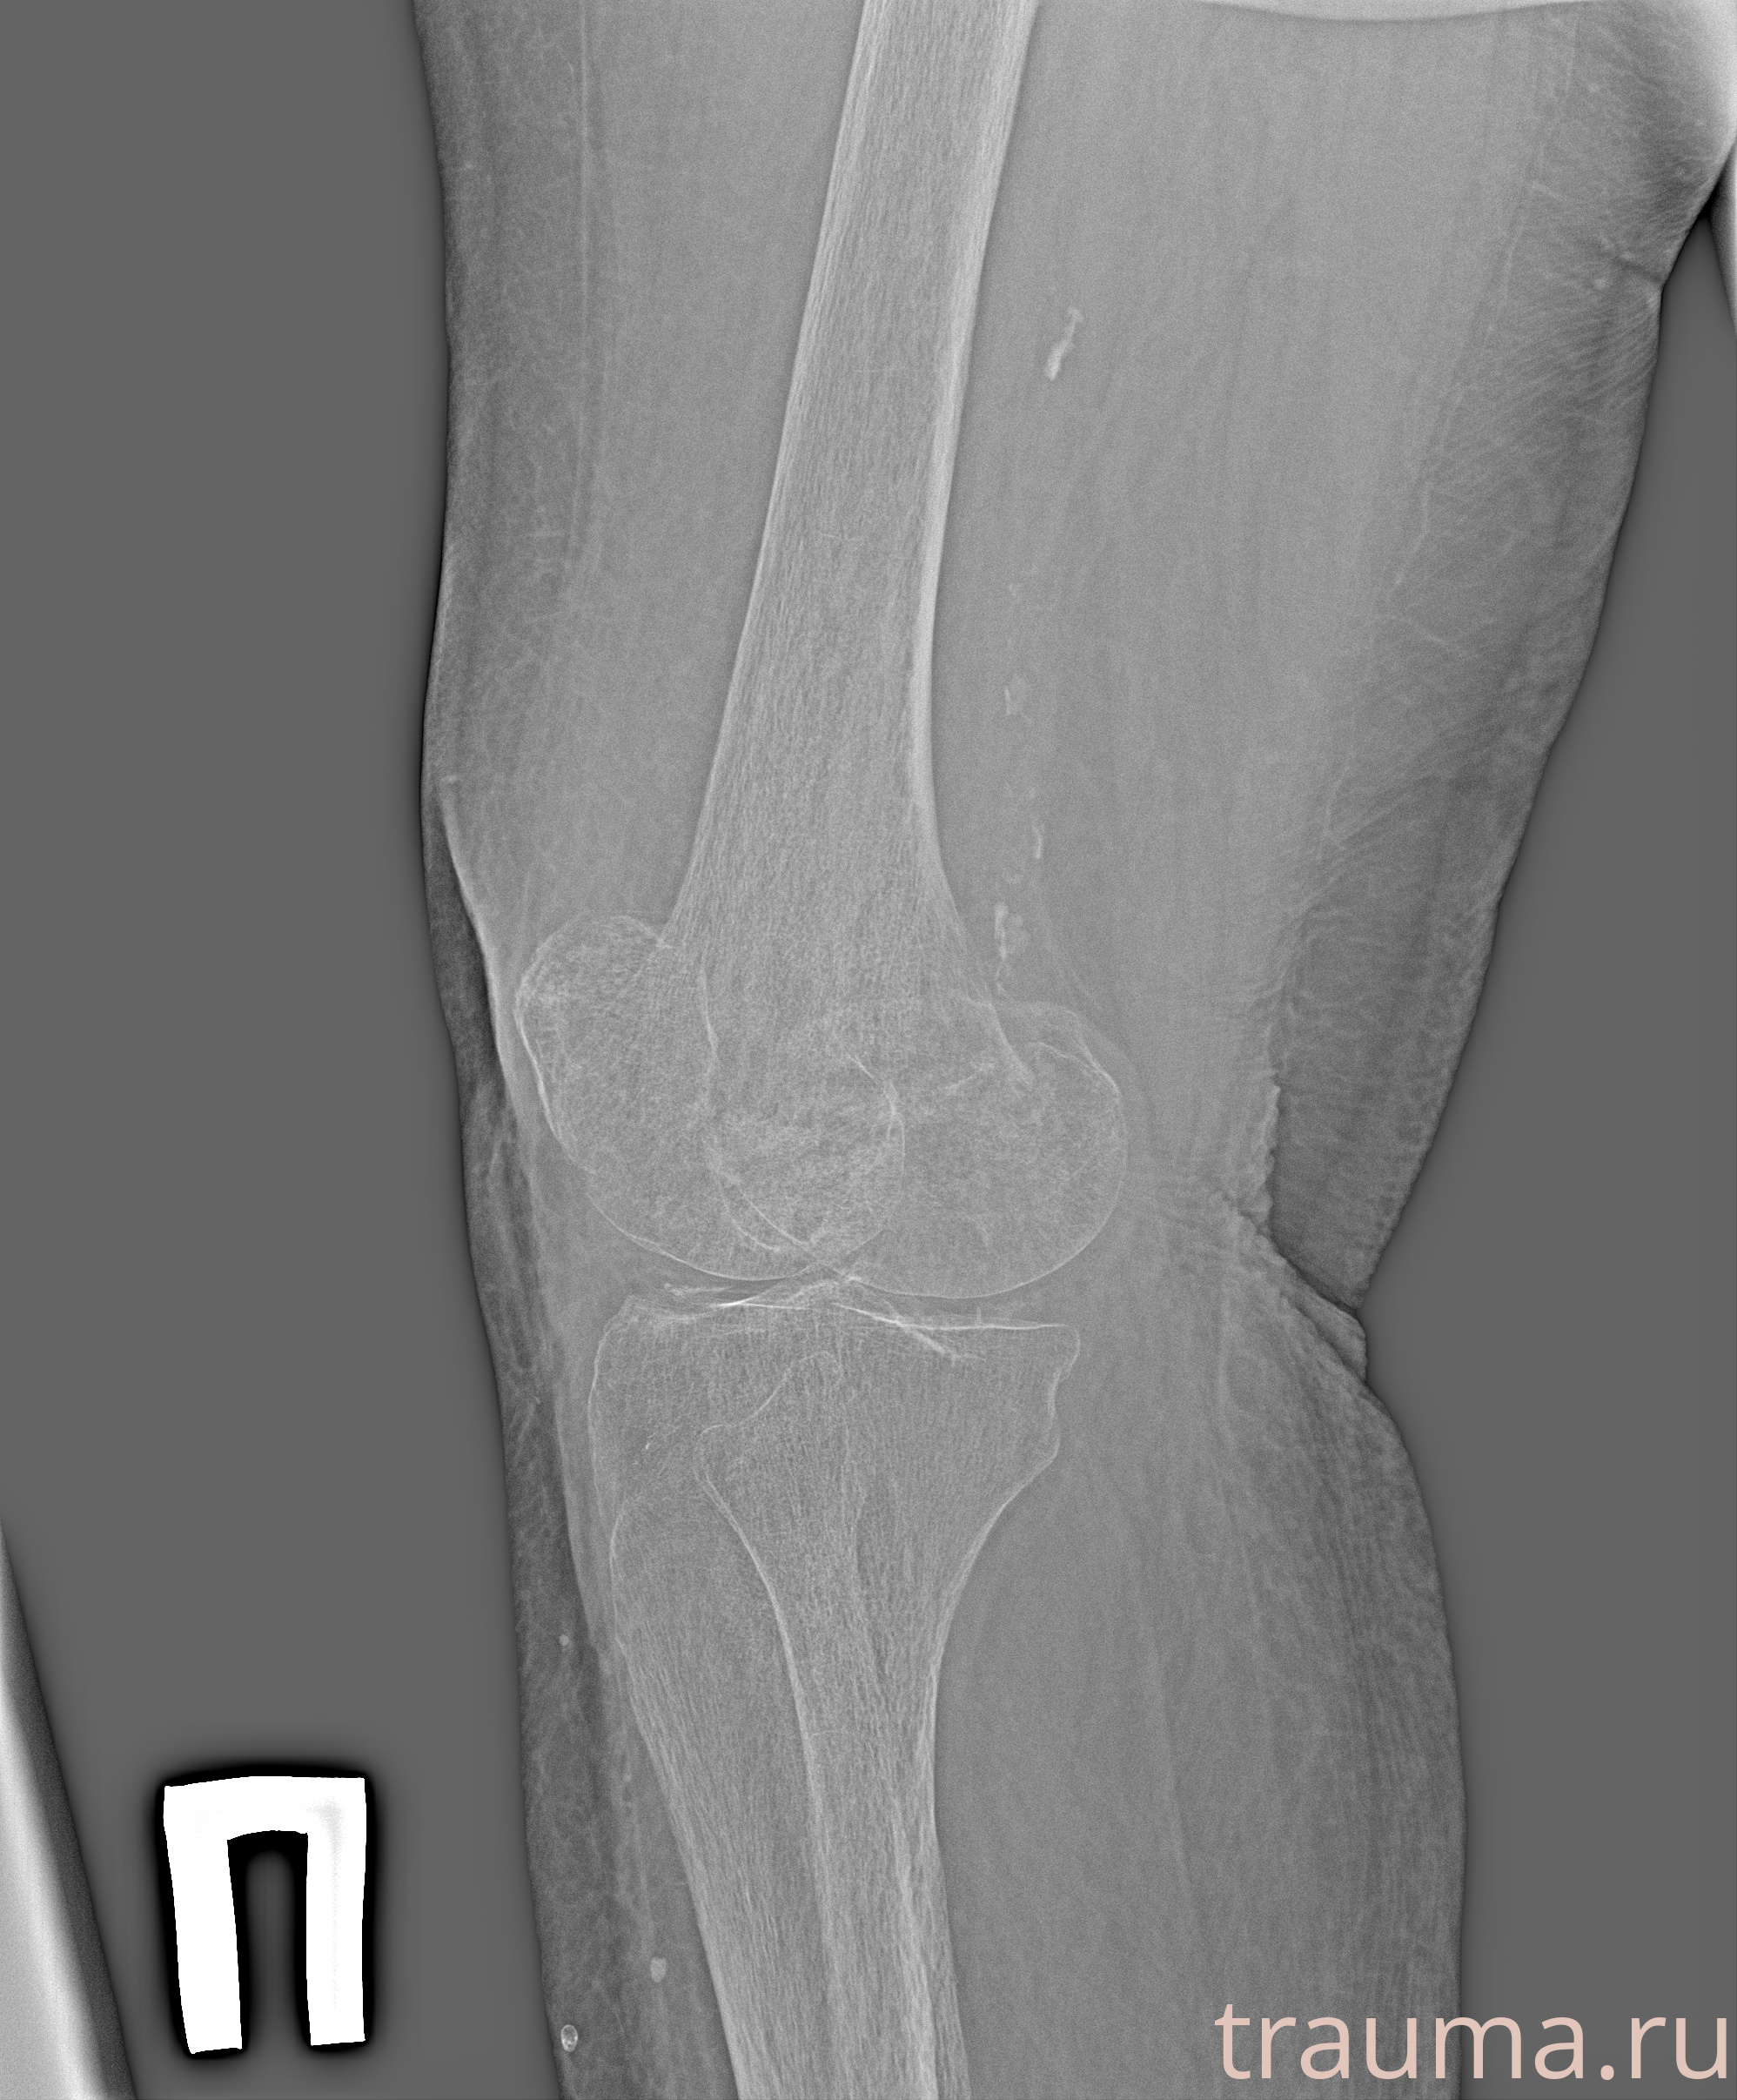

Рентгенограммы

Рентген на дому: по вашему адресу приезжает врач-рентгенолог, травматолог-ортопед с мобильным рентгеновским аппаратом, проводит диагностику травмы или заболевания, делает необходимые рентгенограммы, дает рекомендации по дальнейшему лечению. Получить качественные снимки в домашних условиях возможно благодаря уникальной методике, разработанной МосРентген Центром для института  Склифосовского